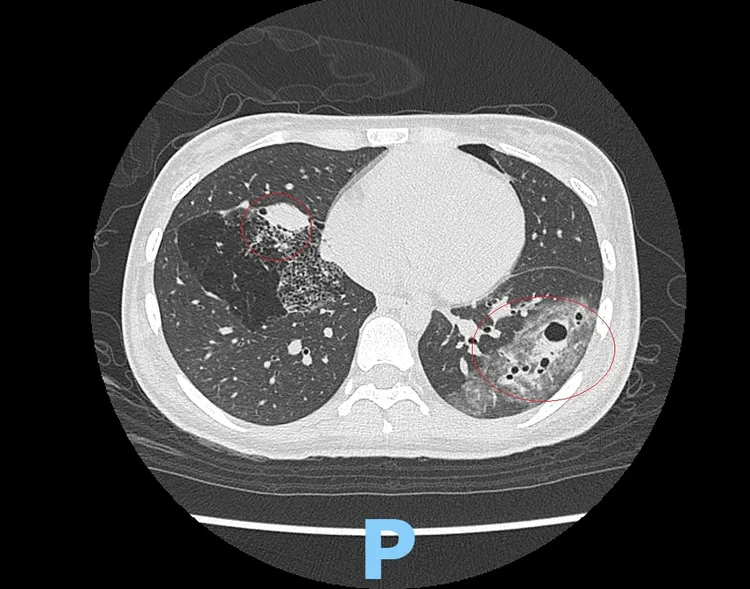

電腦斷層發現黃姓少女左右2肺都有大囊泡、囊腫。彰化醫院提供

馬瑞杉指出,急診發現黃女的肺葉不正常之後,馬上會診胸腔內科及小兒科,排除肺結核、細菌感染的可能後,確定是先天性肺部呼吸道畸形,先住院診治左胸挫傷及四肢擦挫傷,待車禍傷勢好轉後,再進行肺功能呼吸檢測,評估是否手術。

他表示,黃女的個案甚為特殊,不只在產前檢查及新生兒階段沒被發現,也不是因為出現呼吸困難等症狀才被診斷出來,而是因車禍被意外診斷出來,也因為黃女從沒做過胸部X光及電腦斷層檢查,以致此先天疾病被隱藏了16年,所幸黃女沒發生病狀及嚴重感染。